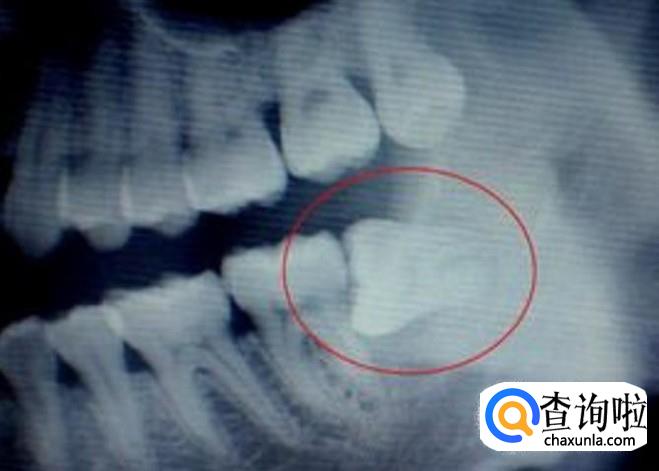

首先,长了智齿的话,如果智齿靠近我们的神经的话,那么这样的智齿是不能拔的,因为如果拔的话,一旦碰到神经的话,那么对我们的身体伤害是巨大的,一般医生也不会建议我们拔的,我们需要定期清理干净我们的智齿处。